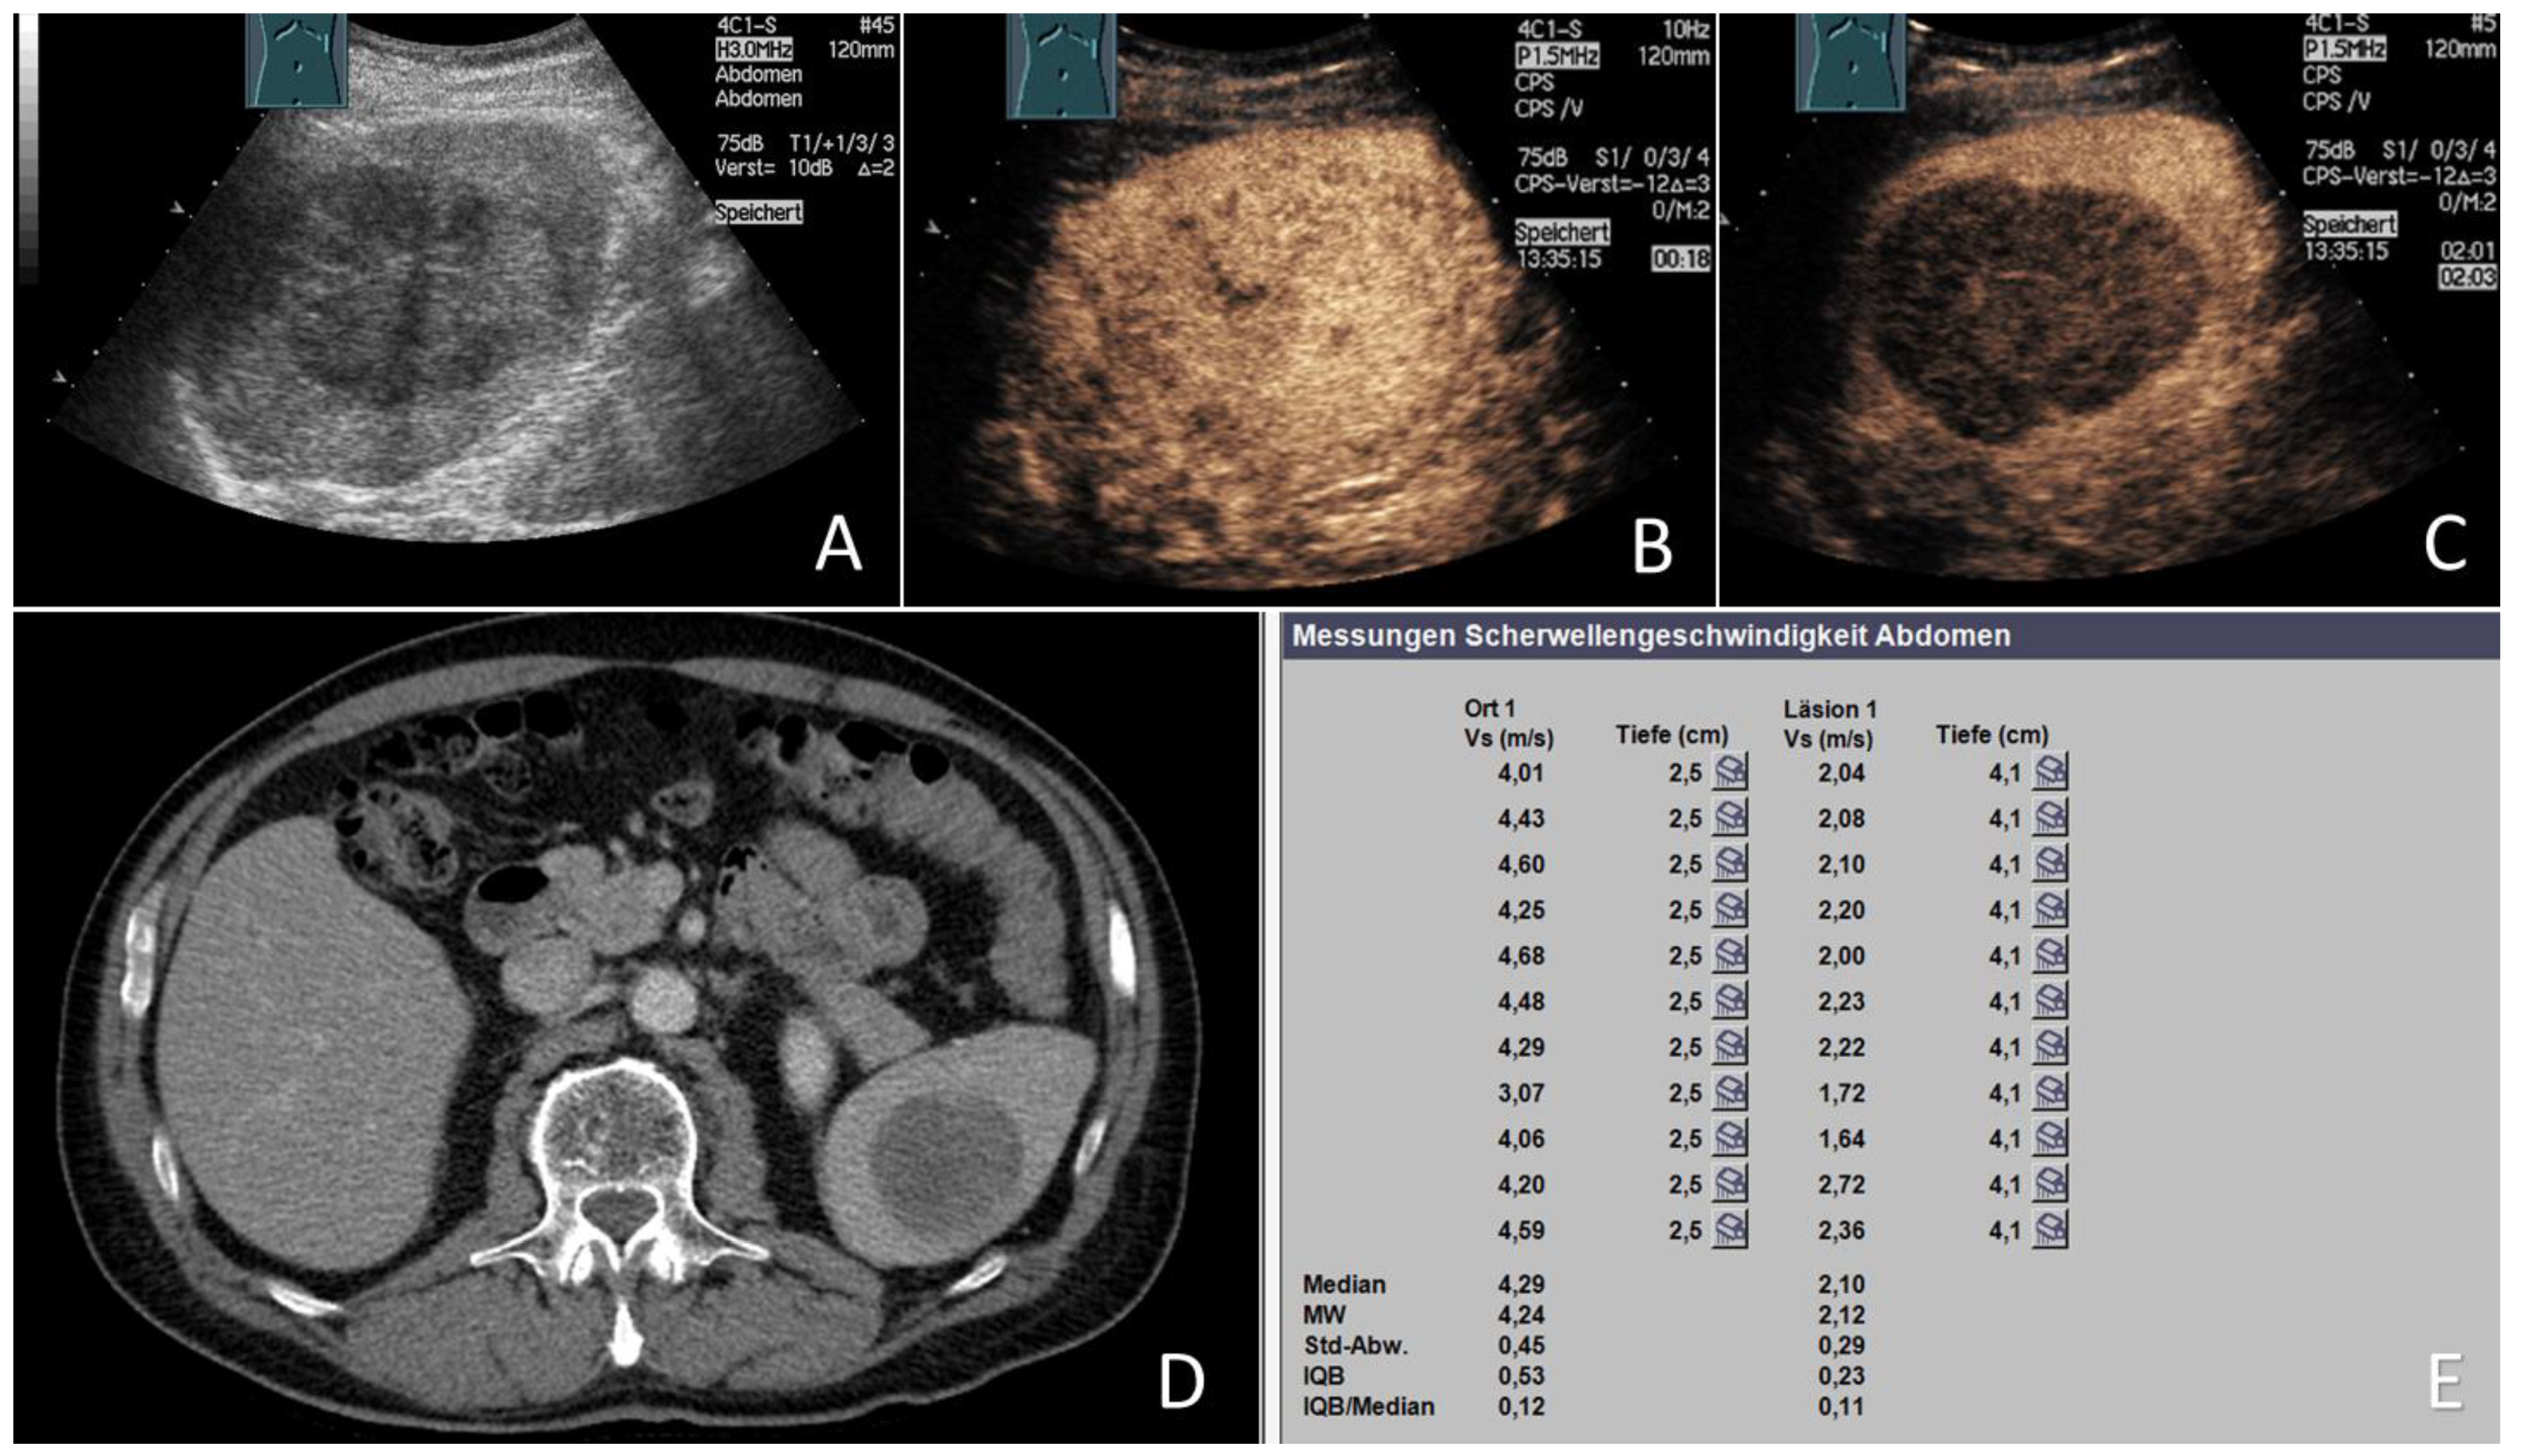

3.5. ARFI Data